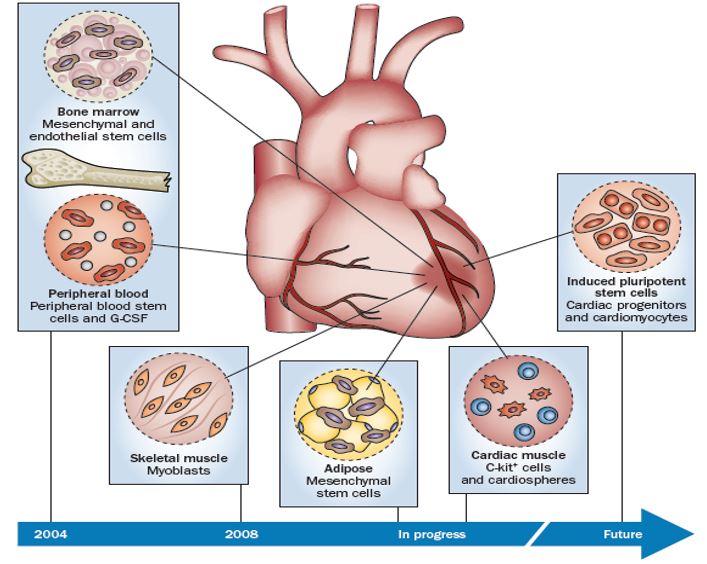

What Is Stem Cell Therapy Dr Amit Nathani MD

Revolutionary Stem Cell Therapy Offers New Hope For Heart Failure Patients

IJMS Free Full Text Cardiac Stem Cell Loaded Delivery Systems A